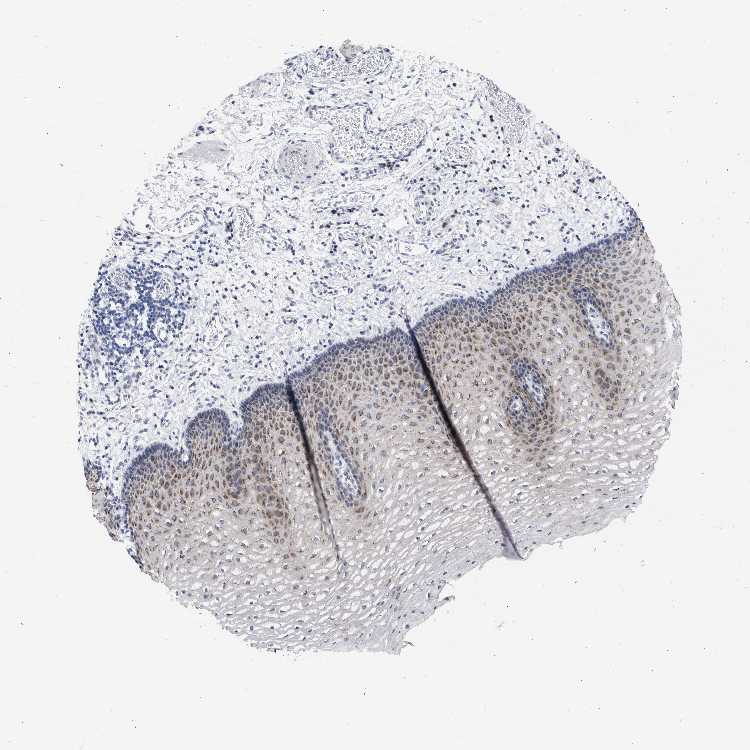

ESOPHAGUS - Antibody stainingi

Antibody staining in the annotated cell types in the current human tissue is reported as not detected, low, medium, or high, based on conventional immunohistochemistry profiling in selected tissues. This score is based on the combination of the staining intensity and fraction of stained cells.

Each image is clickable and will lead to virtual microscopy that enables deeper exploration of all samples and also displays staining intensity scores, fraction scores and subcellular localization as well as patient and tissue information for each sample.

Antibody HPA021178Antibody HPA021230Antibody HPA021799Antibody CAB015421

Squamous epithelial cells MediumMediumMediumLow